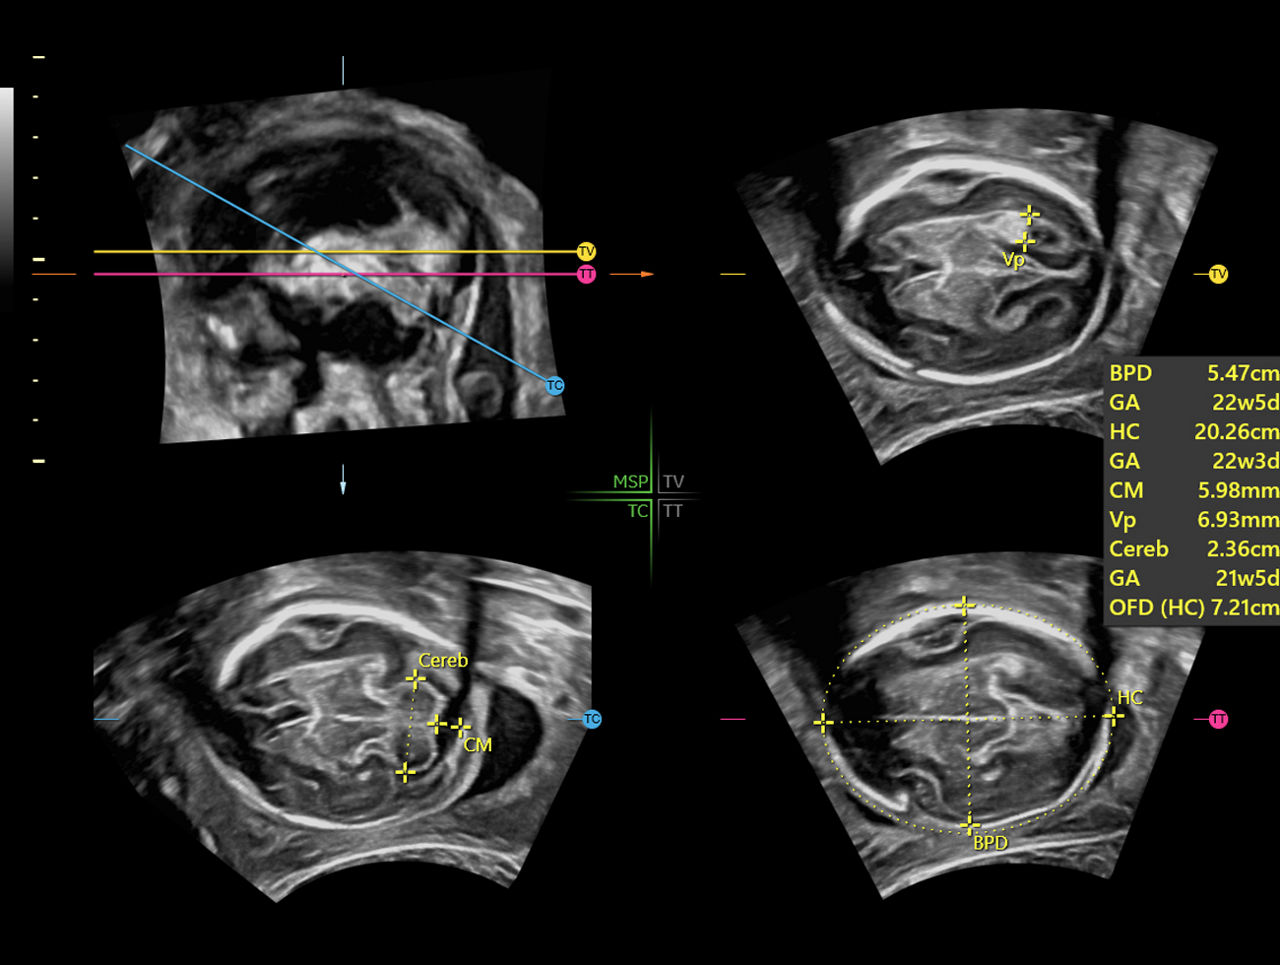

AI driven, SonoCNS supports consistent measurements and helps drive workflow efficiency by helping align and display recommended views and measurements of the fetal brain from a 3D volume

Clinical-Image-of-SonoCNS